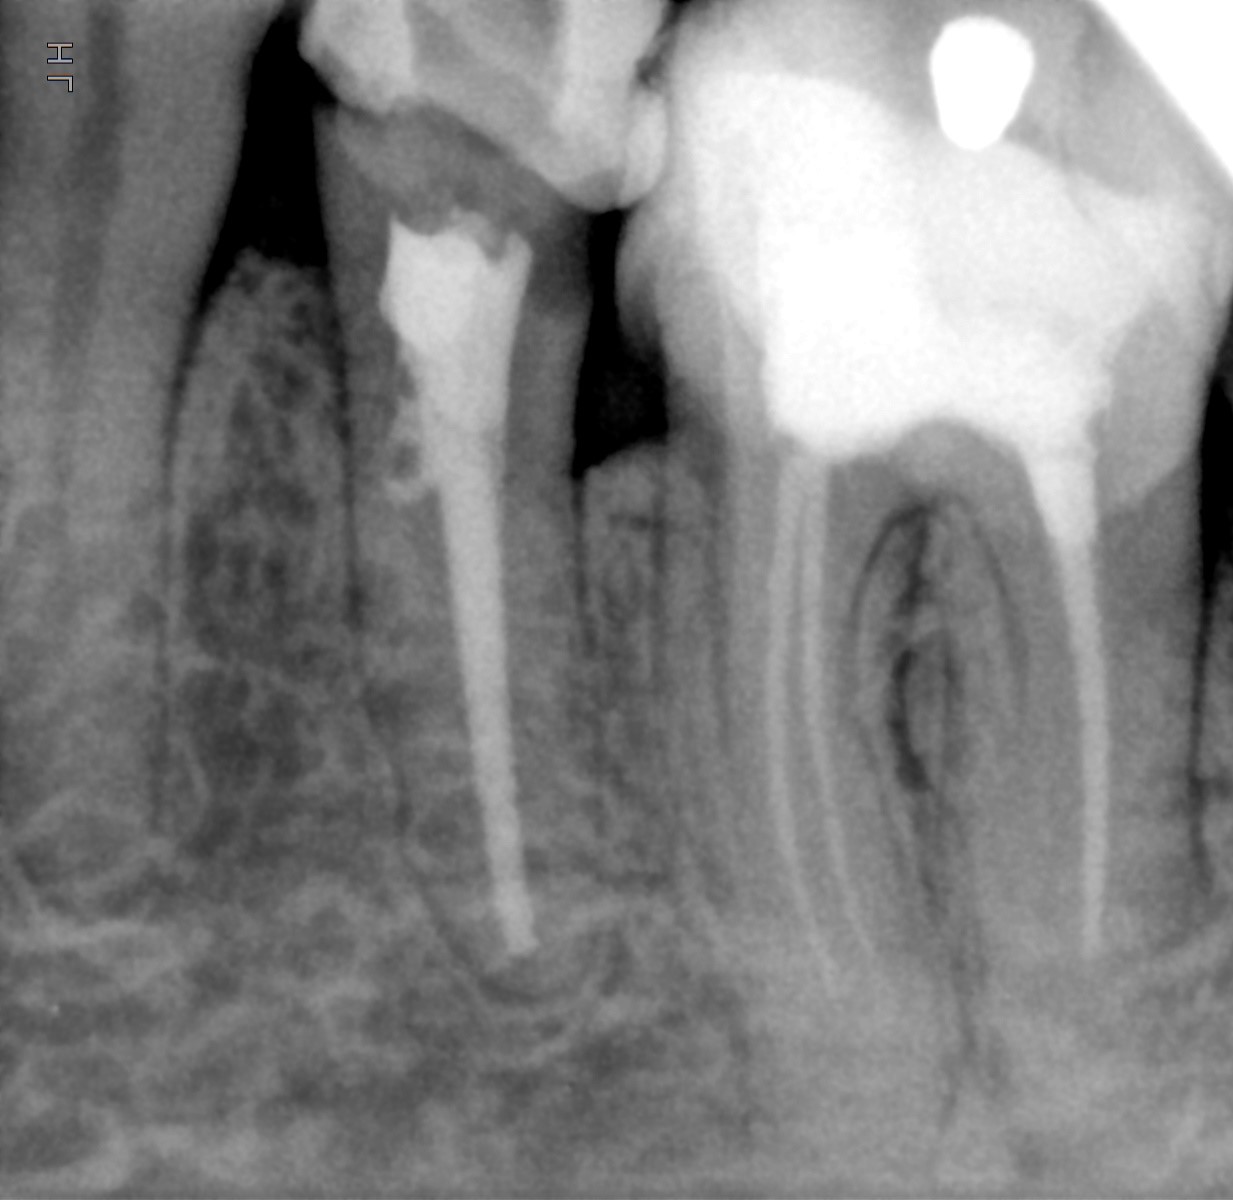

Veja alguns casos de sucesso